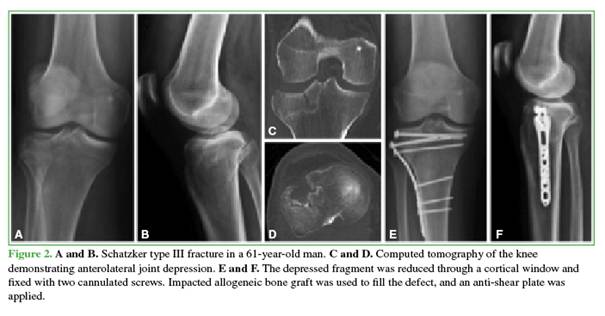

After reduction, preliminary fixation was performed with Kirschner wires. In the rafting technique group (Figure 1), definitive fixation was achieved with 3.5-mm subchondral screws placed through the plate when its design allowed adequate subchondral positioning. When this was not possible, the screws were placed proximally outside the plate.

In the other procedure, the articular surface was restored with impacted bone allograft introduced through a distal window; two cannulated screws (4.5 or 6.5 mm) were then inserted, followed by additional impaction and filling with allograft to occupy the metaphyseal defect (Figure 2).